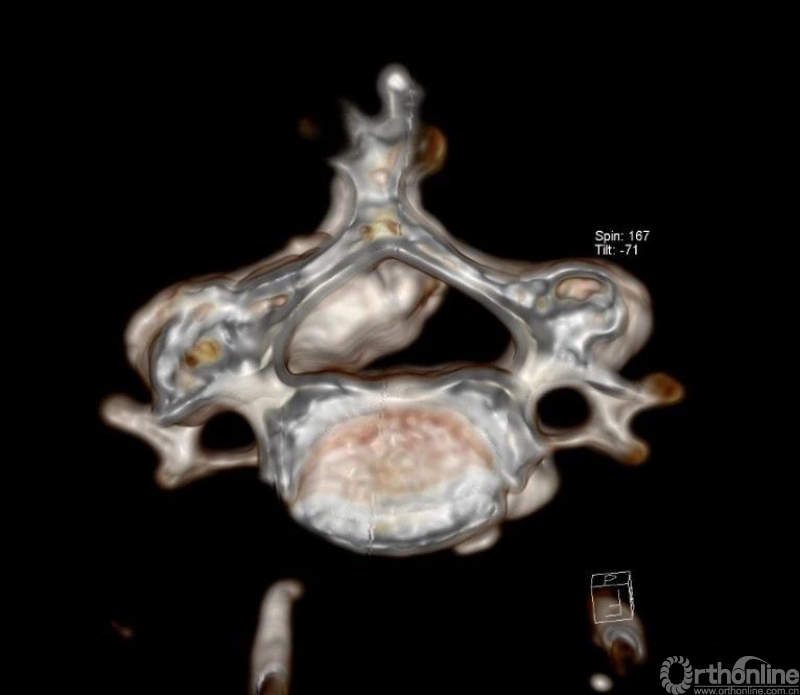

入院查体患者四肢肌张力高,双侧hoffman阳性。CT及MRI检查提示C4/5左侧关节突内缘有一巨大骨块(15mm*16mm),相应节段椎管严重狭窄。椎管内骨块的前端还有一游离骨块。

影像学资料

1.术前评估骨赘侧的椎板间隙几乎完全消失,镜下识别解剖标志困难;

2.在完全看不到骨赘底面的神经结构的情况下磨除骨块风险较大,且神经结构无退路;

3.对侧先椎板切除减压给神经结构一缓冲空间更加安全,并且整个骨块的内侧及上缘、下缘清晰可见。